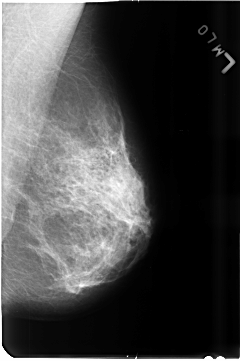

B_3517_1.LEFT_MLO

LEFT_MLO LINES 4688 PIXELS_PER_LINE 3120 BITS_PER_PIXEL 12 RESOLUTION 50 NON_OVERLAY